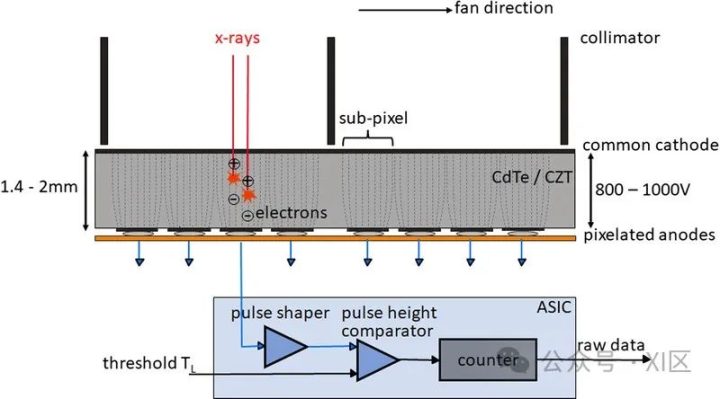

光子计数探测器由碲镉(CdTe)、碲锌镉(CZT)或硅(Si)等半导体制成。由于原子序数较高,碲化镉和碲锌镉层可以相对较薄(1.4-2mm),但仍能提供较高的X射线吸收率。而由硅制成的光子计数探测器则需要更厚(30-60mm)才能充分吸收X射线。根据目前的文献,所有临床前或临床使用的PCD-CT都配备了碲化镉或碲锌镉探测器。图1显示了基于碲化镉或碲锌镉的PCD的结构示意图。在半导体层的上侧是一个大面积的阴极电极,在下侧为像素化阳极电极。在阴极和单个阳极之间施加800-1000 V的高压,可产生强大的电场。入射的X射线被半导体吸收,产生的电荷(电子-空穴对)在电场中分离。电子移动到阳极,在那里产生持续时间约为1 ns(109 s)的短电流脉冲,通过电子脉冲整形电路转换成半宽(FWHM)为10-15 ns的电压脉冲。电压脉冲的脉冲高度与X射线的吸收能量E成正比。一旦脉冲超过阈值TL,即吸收能量(通常为20-25 keV),读出电子装置就会对其进行计数。在技术实现中,使用了一个脉冲高度比较器电路,其中输入了与阈值能量相对应的电压,参见图1。探测器信号相当于在投影测量时间内记录的所有脉冲的总和。

图1 CdTe/CZT PCD(上图)和相应读出ASIC(下图)的示意图。从CT系统的正面看,扇形方向是沿探测器扇形扫描平面的方向。单个探测器像素是由公共阴极和像素化阳极(此处用虚线表示)之间的强电场形成的;像素之间无需进一步分离。在本图所示的探测器结构中,两个准直器叶片之间各有4个子像素,用于抑制散射辐射,另见图4。在ASIC中,被吸收的X射线量子产生的电压脉冲在脉冲高度比较器中与对应于所需阈值能量(20-25 keV)的阈值电压进行比较。只有超过该阈值能量的X射线量子才会被计数。